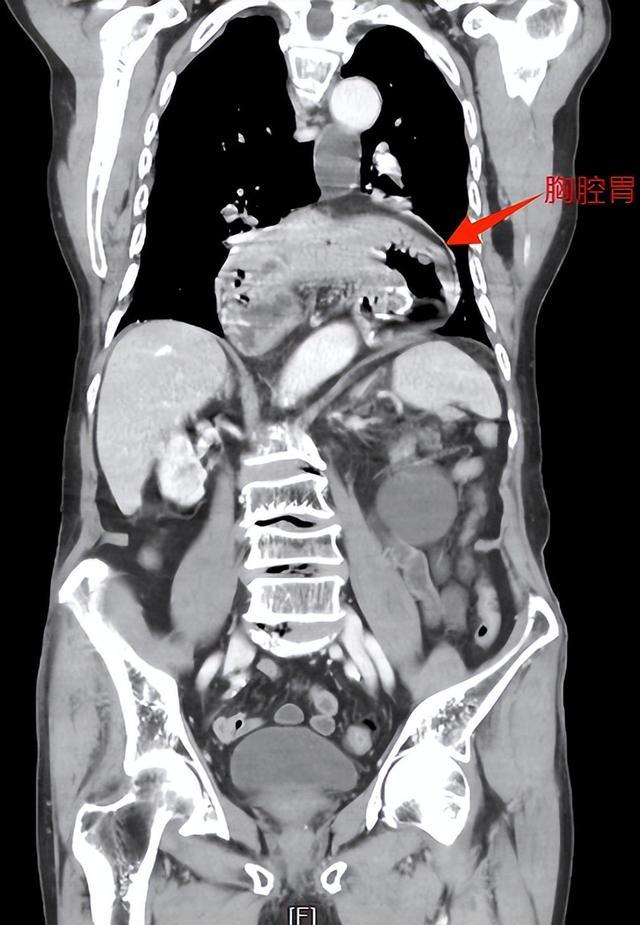

82岁的王爷爷来自湖南岳阳,两三年前开始出现烧心(平躺时尤甚)和进食后呕吐的情况,在当地医院接受护胃、补液等对症治疗,效果甚微。2025年初,老人腹痛、呕吐症状加剧,CT检查发现:他整个胃腔及部分横结肠“顶入”胸腔,形成“胸腔胃”。

▲术前,胃及横结肠“顶入”胸腔